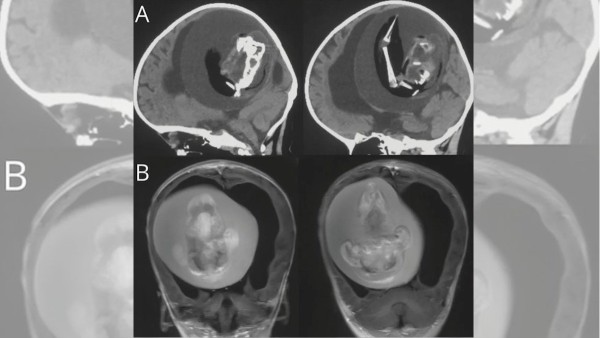

Los médicos se percataron de la situación cuando la niña comenzó a presentar síntomas de retraso en el desarrollo de sus habilidades motoras, así como por un agrandamiento extraño craneal y acumulación de líquido en el cerebro.

Una vez realizados los estudios, decidieron hacer la cirugía donde localizaron al gemelo, mismo que ya mostraba dos huesos de la pierna, una columna vertebral y dedos en las extremidades superiores.